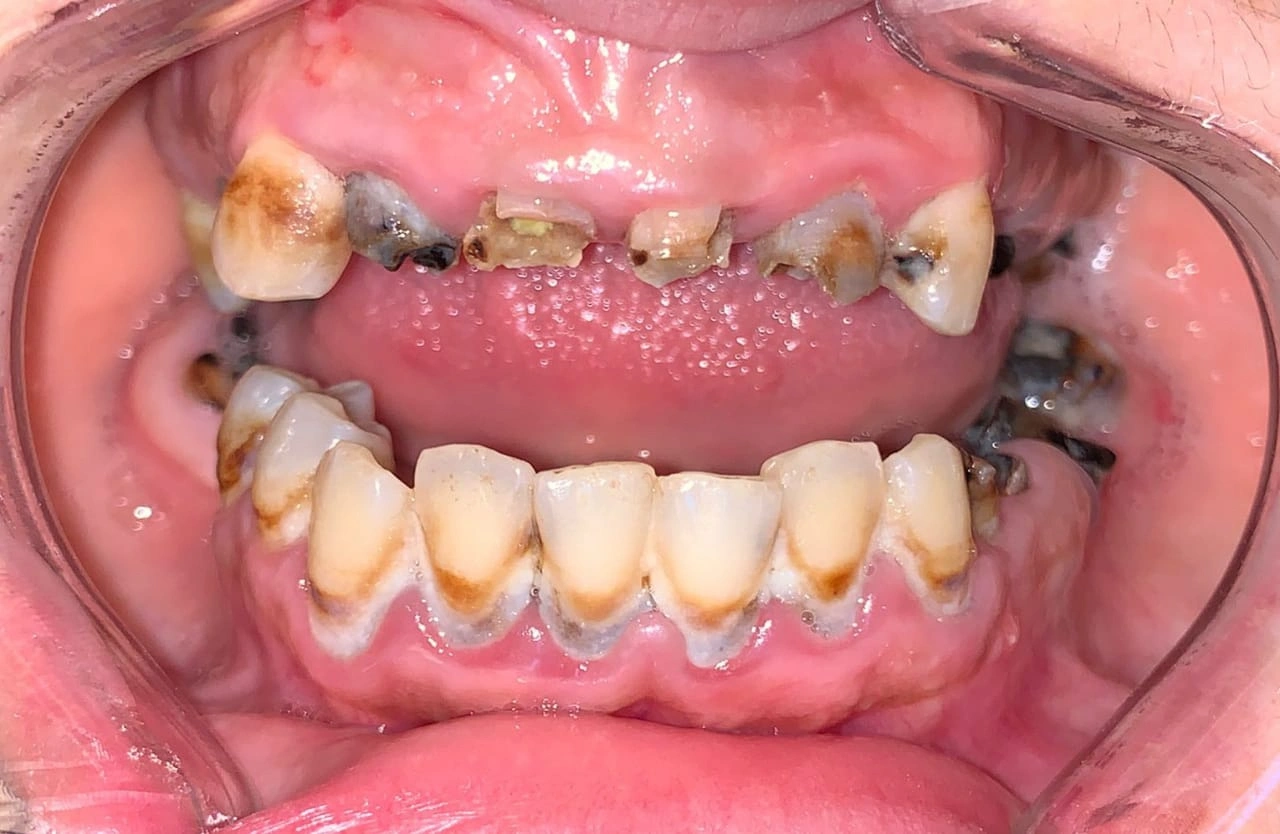

Clinical Cases